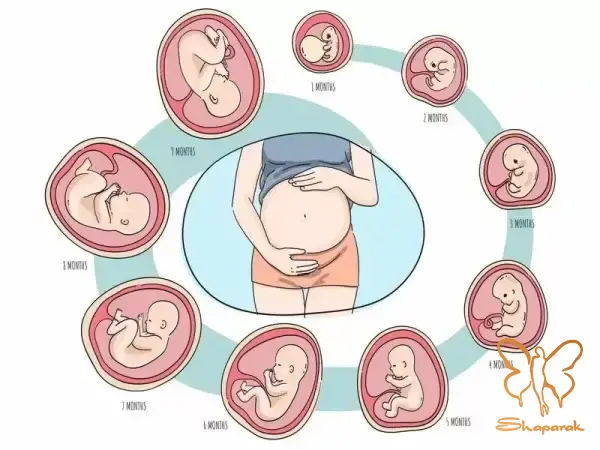

بارداری فرآیندی پیچیده و دقیق است که با لقاح آغاز می شود. در هفته های اول، این سلول به سرعت تقسیم شده و توده ای سلولی را تشکیل می دهد که در دیواره رحم لانه گزینی می کند. در کلینیک تخصصی لیزر موهای زائد شاپرک طلایی مشهد، ما معتقدیم درک این فرآیند ظریف به مادران کمک می کند تا دلیل احتیاط های پزشکی ما را بهتر درک کنند. هر گونه تداخل خارجی، استرس یا ورود مواد شیمیایی ناشناخته در این مراحل اولیه (به ویژه سه ماهه اول که اندام های حیاتی در حال شکل گیری هستند) می تواند ریسک های جبران ناپذیری ایجاد کند. برای درک اینکه چرا خدمات زیبایی مانند: تزریق ژل، بوتاکس یا مواد مزوتراپی و... در دوران بارداری ممنوع است، باید بدانیم جنین چگونه تغذیه می کند. جفت (Placenta) عضوی شگفت انگیز است که رابط بین خون مادر و خون جنین است. اکسیژن و مواد مغذی از طریق بند ناف به جنین می رسد و مواد زائد دفع می شود. اگرچه جفت مانند: یک فیلتر عمل می کند، اما سدی نفوذناپذیر نیست. بسیاری از داروها، مواد شیمیایی ریزمولکول و حتی هورمون های استرس می توانند از سد جفت عبور کرده و وارد جریان خون جنین شوند.